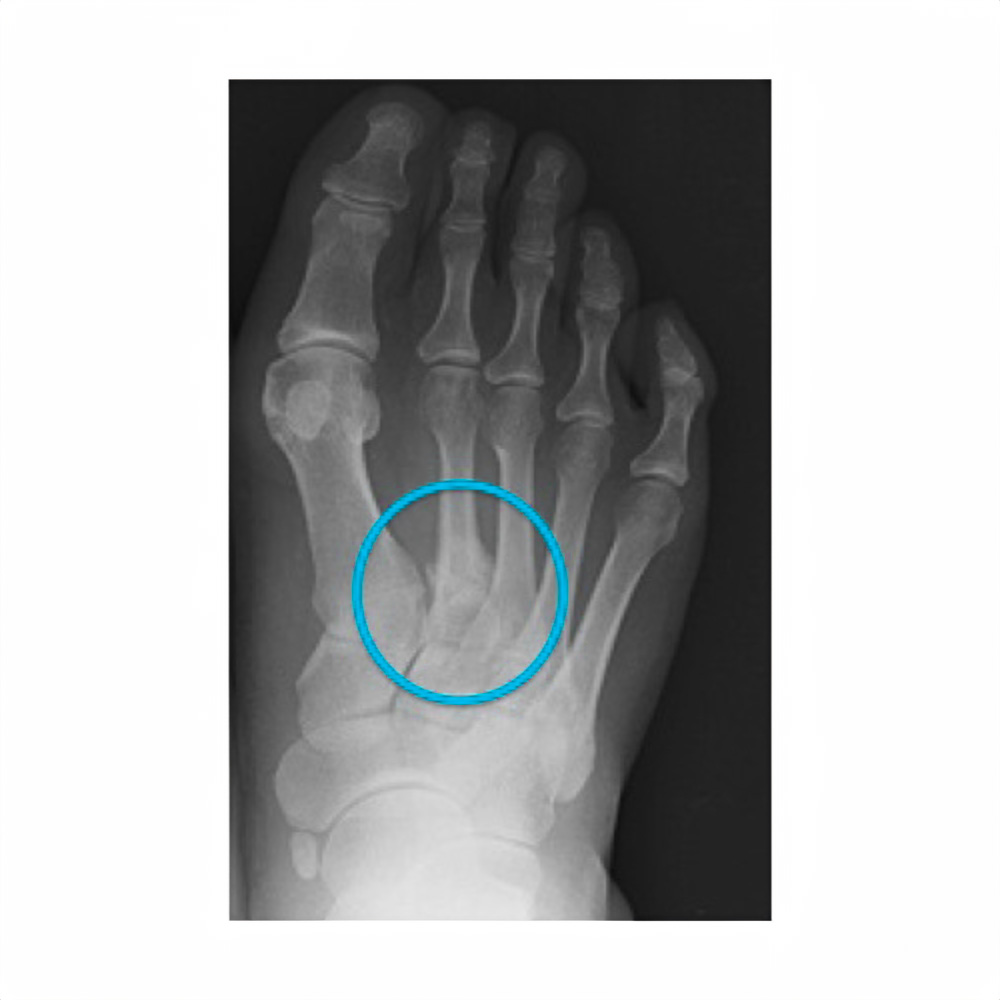

활동을 중단하게 된 이유는 발등 부상으로 알려졌습니다. 연습 도중 통증을 느껴 검사를 해본 결과 발등 미세 골절로 판정이 되었는데 현재로서는 복귀 및 컴백 일정이 불확실한 상태라고 합니다. [참고] 미세골절은 엑스레이에서도 잘 보이지 않을 정도로 실금이 간 상태를 말하는데 방치될 경우 균열이 더 커질 수 있는 것으로 알려져 있습니다.